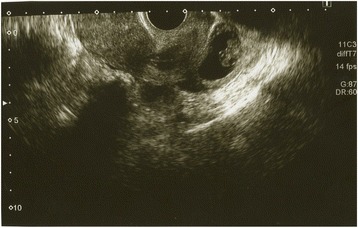

Transvaginal ultrasound was performed and a gestational sac (GS) could not be located in the uterus, but there was a GS containing a fetus consistent with 8 weeks 6 days of gestation (crown rump length: 18.8 mm) near the pouch of Douglas. (Fig. 1) An EP was diagnosed, and the patient was transported to another hospital because our clinic does not have an operating room suitable for laparoscopy. The laparoscopic diagnosis was an unruptured AEP of the pouch of Douglas. (Fig. 2). The gestational tissue was removed by forceps, and electrocauterization was used for hemostasis under laparoscopic surgery. The serum β-HCG was less than 0.5 IU/L 33 days after surgery.

Fig. 1.

Ultrasound of gestational sac near Douglas cavum